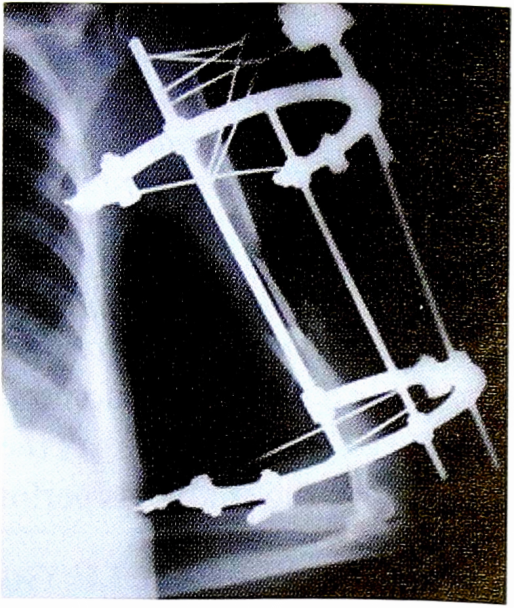

Pиc. 7. Оперативное лечение пациентки И.: пластика левой плечевой кости свободным кровоснабжаемым трансплантатом из малоберцовой кости.

Fig. 7. Surgical treatment of patient I.: plastic left humerus free perfused transplantthat of the fibula.